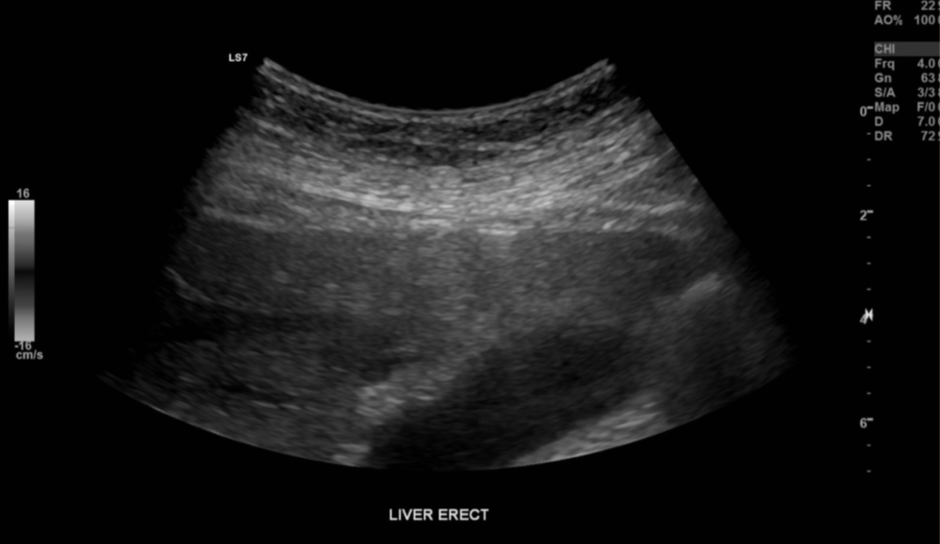

Figure 2. Example of the subtle nature of small pockets of intraperitoneal air. |

Note how the two linear strong reflectors at the liver capsule differ from the rest of the liver margin.

Upon scanning, the patient was acutely tender in the epigastrium. When lying in the left posterior oblique position, ringdown artifact starting just superficial to the left lobe of the liver was noted. This artifact was subtle but reproducible when scanning in different positions and corresponded to the patient’s main region of pain.